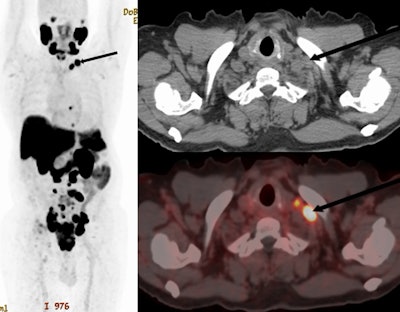

F-18 PSMA-1007 PET/CT of a 70 year old with newly diagnosed prostate cancer: PSA 770 ng/ml; Gleason 5 + 5; International Society of Urological Pathology grade 5. The maximum intensity projection images, CT, and fused images show PSMA ligand-avid prostate primary with pelvic, retroperitoneal, and mediastinal nodal spread. Additionally, he had left supraclavicular nodal metastasis (arrows). Image and caption available for republishing under Creative Commons license (CC BY 4.0 DEED, Attribution 4.0 International) and courtesy of EJNMMI Reports.F-18 PSMA-1007 PET/CT of a 70 year old with newly diagnosed prostate cancer: PSA 770 ng/ml; Gleason 5 + 5; International Society of Urological Pathology grade 5. The maximum intensity projection images, CT, and fused images show PSMA ligand-avid prostate primary with pelvic, retroperitoneal, and mediastinal nodal spread. Additionally, he had left supraclavicular nodal metastasis (arrows). Image and caption available for republishing under Creative Commons license (CC BY 4.0 DEED, Attribution 4.0 International) and courtesy of EJNMMI Reports.

According to the findings, the prevalence of SC nodal metastasis in the cohort was 7.9% (n = 19/240). A majority of those with SC nodal metastasis, 84% (n = 16/19) also had associated skeletal metastasis and one patient with SC nodal disease had associated visceral metastasis in the lungs, the group added.